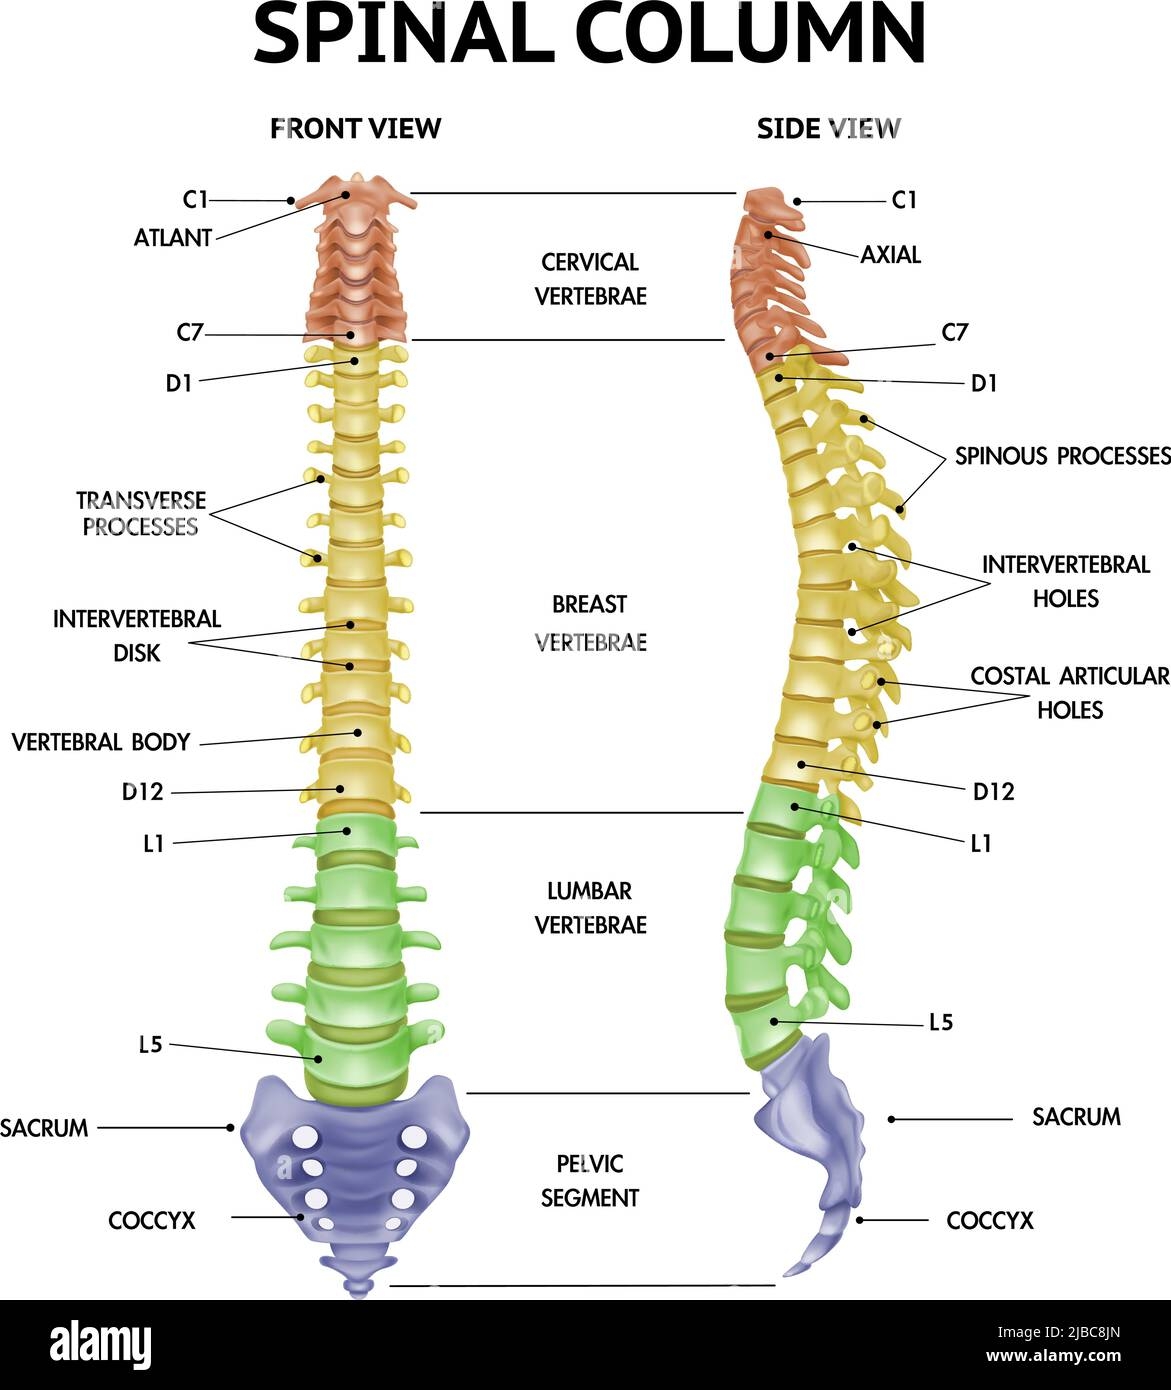

The Vertebral Column Anatomical Chart is a detailed illustration that breaks down the spine into its individual components. From the cervical spine in the neck to the coccyx at the base, each vertebra plays a unique role in supporting the body and allowing for movement.

By studying the Vertebral Column Anatomical Chart, healthcare professionals, students, and individuals can learn about the different regions of the spine, including the curvature of the vertebrae, the function of intervertebral discs, and the role of spinal nerves in transmitting signals throughout the body.

Spinal Column Anatomy Side Front Views Realistic Info chart